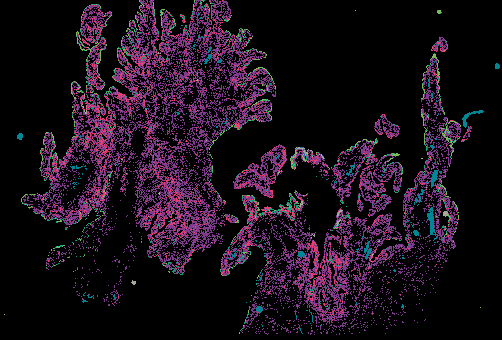

Ovarian STIC Spatial Transcriptomic Data from GeoMX and Multiplex Imaging

Ovarian Cancer with Annotation - LSP15327

Ovarian Cancer with Annotation - LSP15343